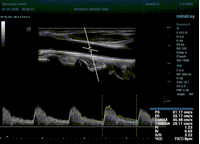

Какие показатели выдает автоматический расчет? Доктор может настроить расчет под себя, под свои собственные желания. Стандартно выставлены показатели пиковой (PS) и конечной диастолической скорости (ED), TAMAX, TAMEAN, Pi, Ri, S/D соотношение и ЧСС. Можно дополнить из списка показателей: MD, PPG, Объемный поток, DT, AT, MPG, MMPG, VTI, D/S соотношение. Прибор подстраивается под Вас, а не вы под прибор.